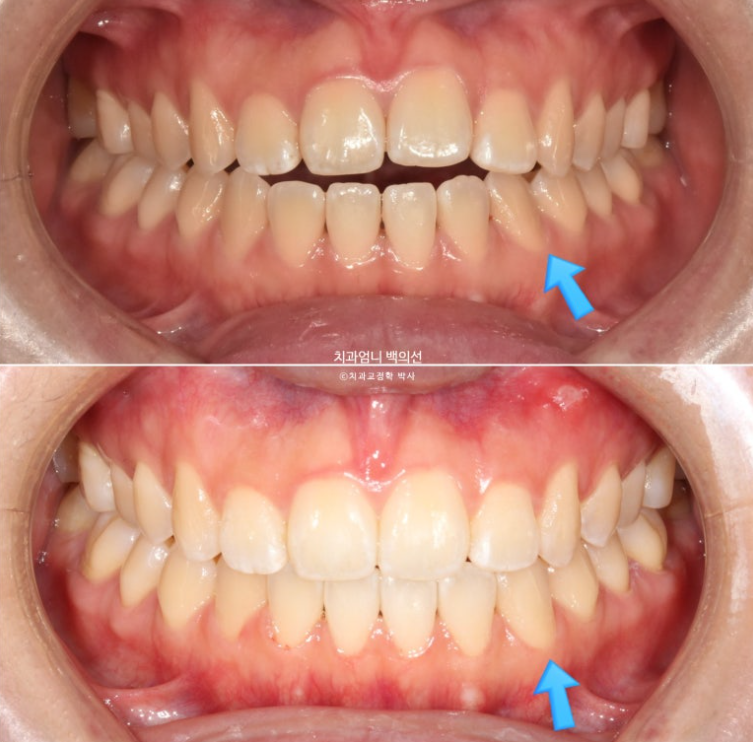

파란 화살표 송곳니는 안쪽으로 쓰러져 있습니다.

파란 화살표 접착제가 까맣게 보이는 것은 접착제가 치아와 분리된 상태이기 때문입니다.

맞아진 앞니 높낮이와 적절한 앞니 교합

앞니 개방교합이 깔끔하게 해결되었습니다.

이제 전후 비교 보겠습니다.

24.12~25.06

개방교합 뿐 아니라 철사의 변형으로 쓰러져 있던 송곳니도 세웠습니다.

6개월간 앞니 부분교정의 변화 치고 드라마틱 합니다.